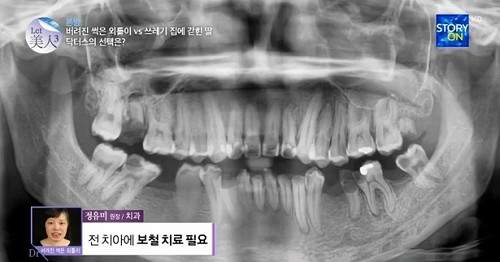

在醫生的診療之下,她的牙齒的狀況真的很糟..........

她32顆牙齒中,就有12顆已壞死必須拔掉,看來又是個大工程啊..........